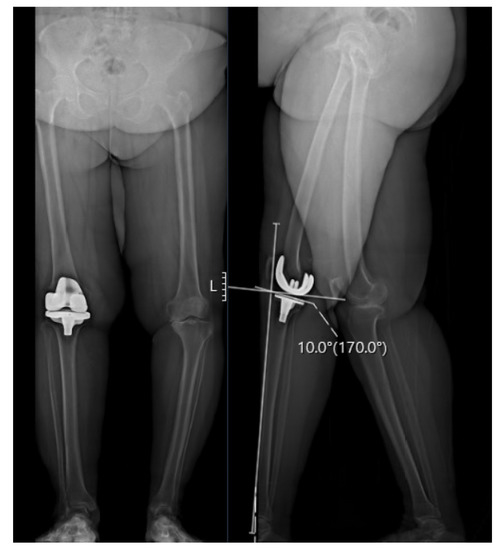

2.2. Radiographic Analysis

| PTS | 9.6 (5.4) | 11.79 (5.4) | 0.001 | 2.87 (1.8) | 9.19 (2.9) | <0.001 |

| MPTA | 85.14 (3.3) | 85.2 (3.6) | 0.876 | 86.14 (3.02) | 86.64 (3.1) | 0.16 |

| LDFA | 89.53 (3.8) | 89.46 (4.02) | 0.889 | 85.64 (4.7) | 84.22 (3.7) | 0.007 |

| HKA | 9.47 (4.83) | 10.24 (5.02) | 0.185 | 2.91 (2.9) | 1.92 (3.44) | 0.029 |